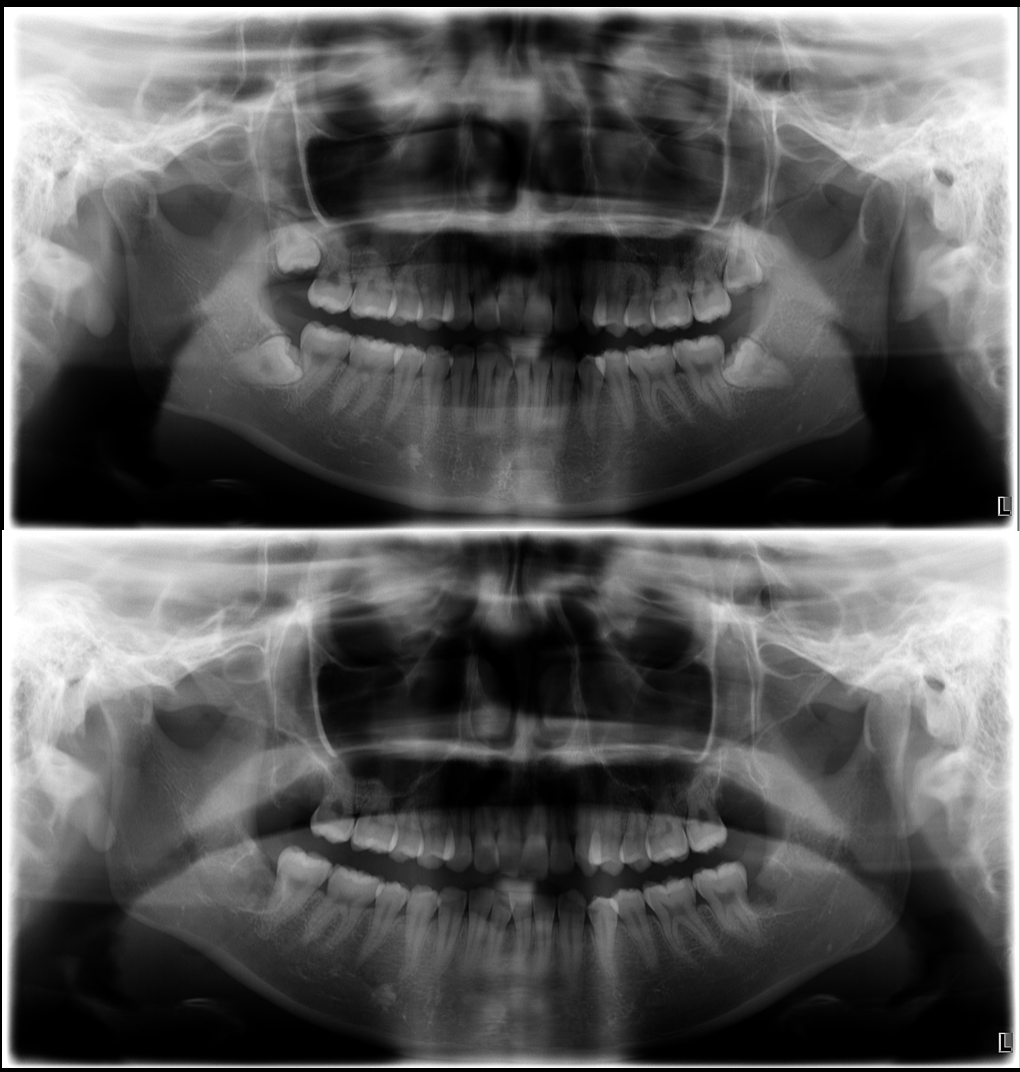

医院ブログ2025.11.13

池袋で歯周病の非外科治療なら|グランドメゾンデ...